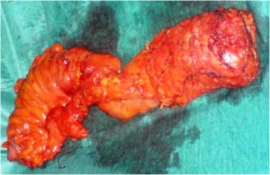

Εισαγωγή- Ορισμός Η πρόπτωση του ορθού (procidentia) αποτελεί, αναντίρρητα, μια νοσολογική οντότητα με αναπηρική επίδραση στην ποιότητα ζωής του/της άτυχου ασθενούς. Η παρουσία της έχει δυσμενείς συνέπειες στις λειτουργίες της αφόδευσης και της εγκράτειας των κοπράνων. Το γεγονός ότι 100 περίπου χειρουργικές επεμβάσεις έχουν περιγραφεί για τη χειρουργική αποκατάσταση της…